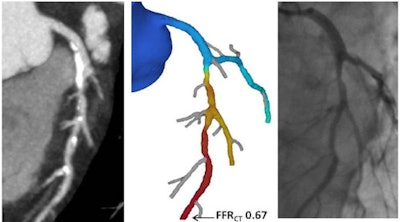

FFR-CT had higher diagnostic accuracy than CCTA (83% versus 29%) with higher positive predictive value (69% versus 29%). All images courtesy of Dr. Kristof De Smet.CCTA is a great tool for evaluating young patients with chest pain and for those with a low and intermediate risk of heart disease, but by itself it is inadequate for confirming obstructive coronary disease that requires intervention, he said. And even though CCTA results correlate well with angiography with regard to stenosis severity, CT cannot reliably estimate the hemodynamic significance of lesions.

FFR-CT adoption produced a sixfold reduction of false positives."It takes into account the morphology from the coronary tree, takes into account the muscle of the heart, and then based on fluid dynamics gives us a number, a quantification for each part of the coronary tree. Any result below 0.8 for a vessel means there's a problem and the patient requires revascularization.

The results showed that FFR-CT had 83% diagnostic accuracy versus 29% for CCTA, with a higher positive predictive value of 69% versus 29% and a sixfold reduction in false positives, from 34 with CCTA to five with FFR-CT.

Fractional flow result of 0.67 (center) based on computational fluid dynamics reveals hemodynamically significant lesions requiring revascularization.Moreover, noninvasive FFR-guided therapy revealed that 71% of patients (34 of 48) had nonobstructive coronary disease (FFR > 0.8) and could be treated medically. Another 14 patients (29%, 14 of 48) had FFR of 0.8 or lower and underwent revascularization -- eight with percutaneous coronary intervention (PCI) and six with coronary artery bypass grafts (CABG). No adverse events were recorded.